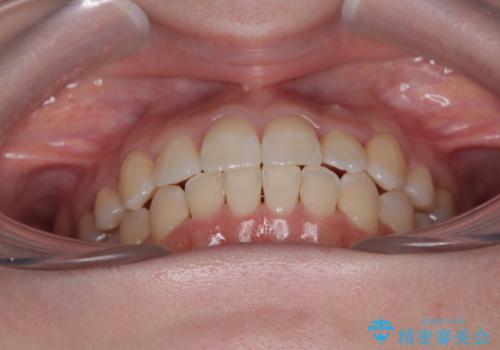

補助装置を併用したおかげで、出っ歯になることなくスムーズに治療を終えることができました。

上顎前歯部はデコボコが強く、歯を並べるためのスペースが不足しているため、左右の第一小臼歯を抜歯することとしました。

また、抜歯して確保したスペースが不足してしまうのを防ぐため、補助装置を併用しています。